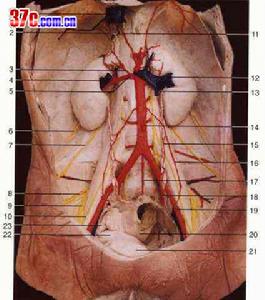

腹膜後間隙可按解剖部位簡易地分為五個區域:①腎周間隙;②上腹膜後間隙;③盆腔間隙;④下腹膜後聯和盆腔間隙;⑤局限性肌肉-骨骼間隙,以利分析影響後果的因素。

感染或膿腫一般局限在某原發部位,但可能向對側或由一個間隙向另一間隙播散。少數情況亦可沿筋膜平面或穿透膜向遠處擴散,如深部骨盆腹膜下;腸系膜根部;股、髖、前腹壁、背及脅皮下組織;膈下、縱膈及胸腔;甚至形成瀰漫性後腹膜感染,引起蜂窩組織炎並致壞死。